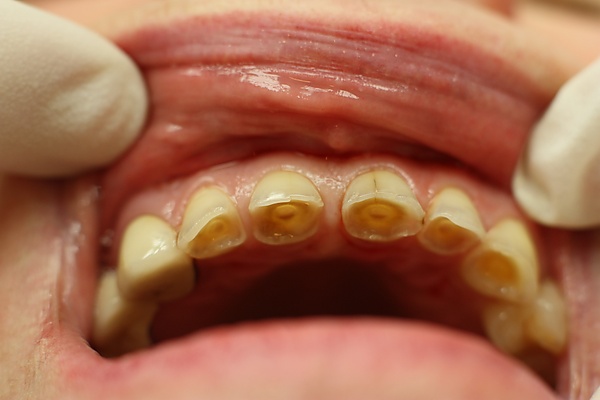

В отличие от физиологической стираемости зубов, патологическая стираемость характеризуется более ранней и значительно выраженной потерей твёрдых тканей, которая чаще носит генерализованный характер и отмечается на всех зубах. При патологической стираемости зубов наблюдается стирание эмали и дентина, доходя до шейки зубов, причем после обнажения дентина её стирание идет более интенсивно, так как дентин — более мягкая ткань. В результате этого по краям зуба образуются острые края эмали, которые часто травмируют слизистую оболочку щёк и губ. Если лечение вовремя не проводится, то стирание быстро прогрессирует и зуб становится значительно короче. В таких случаях наблюдаются признаки уменьшения нижней трети лица: складки у уголков рта, изменение височно-нижнечелюстного сустава, боль в области височно-нижнечелюстного сустава и языка, снижение слуха.

При начальных проявлениях патологической стираемости зубов появляется чувствительность к температурным раздражениям, а по мере углубления процесса появляются боли от химических и механических раздражений. По внешним клиническим проявлениям традиционно различают горизонтальный, вертикальный и смешанный тип стираемости зубов.[1]:72. При этом убыль тканей происходит либо в горизонтальной плоскости, тогда стираются режущие края зубов, бугры и жевательные поверхности, либо в вертикальной плоскости, и тогда убыль тканей происходит на вестибулярной поверхности зубов. Особо следует отметить, что вертикальная стираемость зубов, как самостоятельная нозологическая единица, встречается крайне редко. Чаще она сочетается с горизонтальной стираемостью, что определяется как смешанный тип стираемости, а также и с другими формами некариозных поражений зубов (эрозиями, клиновидными дефектами). Существует несколько классификаций повышенной стираемости зубов, предложенных разными авторами, но наиболее широкое применение получила классификация М. И. Грошикова (1985), согласно которой выделяют три степени стираемости зубов в зависимости от глубины вовлекаемых в процесс и убывающих (сошлифованных) тканей.[2]:108.